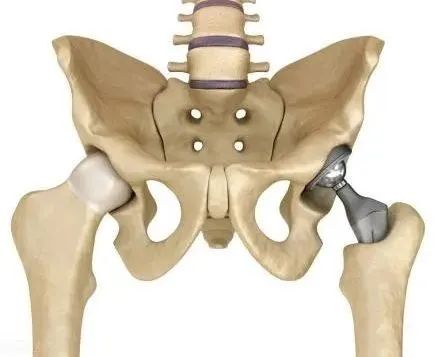

股骨头坏死的治疗目标在于预防股骨头的塌陷,尽可能长时间保留生物髋关节,常见的治疗方法包括非手术治疗和手术治疗。

非手术治疗主要针对股骨头坏死范围比较小且股骨头形状未见塌陷的患者。

术治疗主要针对股骨头坏死明显并且保守治疗无效的患者。手术治疗主要有保髋手术和人工关节置换术,保髋手术主要针对年轻患者以及早期股骨头坏死的患者(ARCOⅠ~Ⅱ期)。人工关节置换主要针对股骨头塌陷严重且保髋治疗无效的患者。